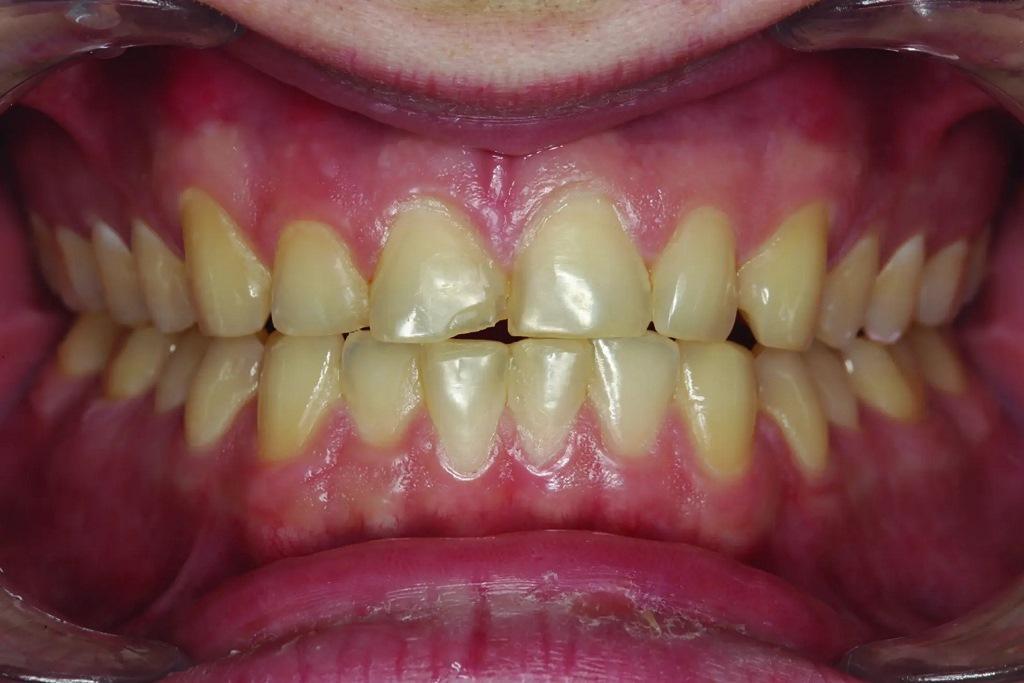

А как насчет выравнивания зубов-антагонистов? На режущих краях зубов 31 и 41 (фото 2) наблюдался чрезмерный износ. Со стороны резцов был виден значительный износ всех краев нижней челюсти из-за окклюзионного заболевания, которое часто наблюдается, но не лечится (фото 3). Также зуб 41 располагался на лицевой стороне таким образом, что при выступающей экскурсии он преждевременно соприкасался с небной поверхностью зуба 11, создавая дополнительную нагрузку как на небную поверхность, так и на резцовый край зуба 11, прежде чем соединиться с остальной частью переднего сегмента верхней челюсти. Это демонстрирует, что решение этих проблем реставрационными методами включает в себя нечто большее, чем просто исправление сколов композитной реставрации.

Фото 3: Резцовый вид показывает, что зуб 41 был наиболее расположенным к лицу резцом нижней челюсти в форме дуги.